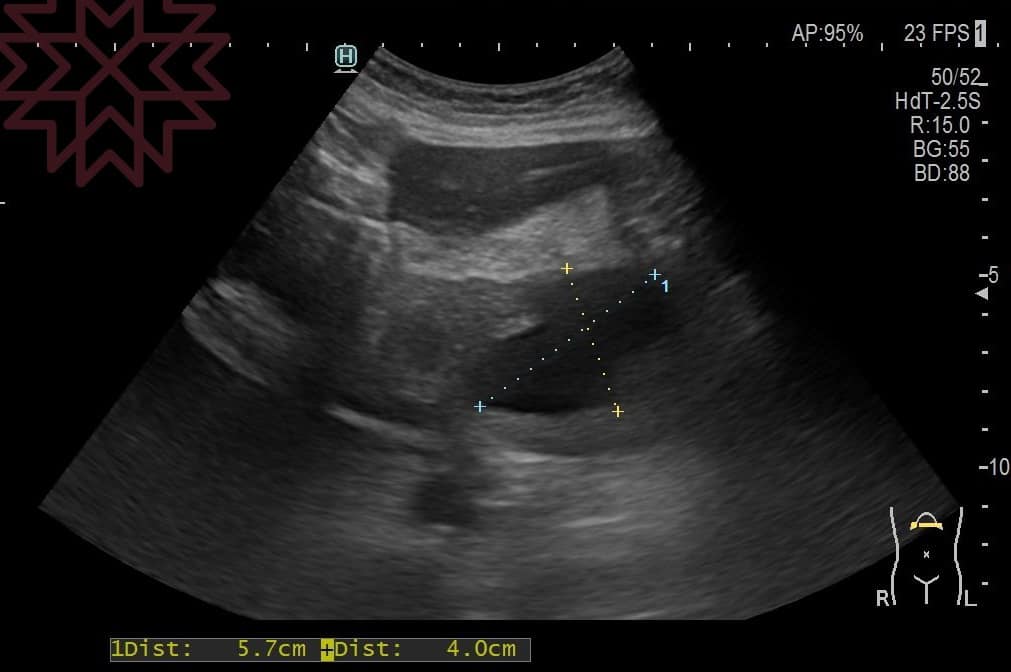

林相宏指出,女子驚覺有異,結果超音波一照,全肚子都是癌症產生的「腹水」,切片確診胰臟癌末期,「這時要如何讓腹水消除、肚子不要發脹呢?我只能說已經腹水難收。」

翻攝自臉書 (胰臟醫師 林相宏 禾馨民權內科診所)